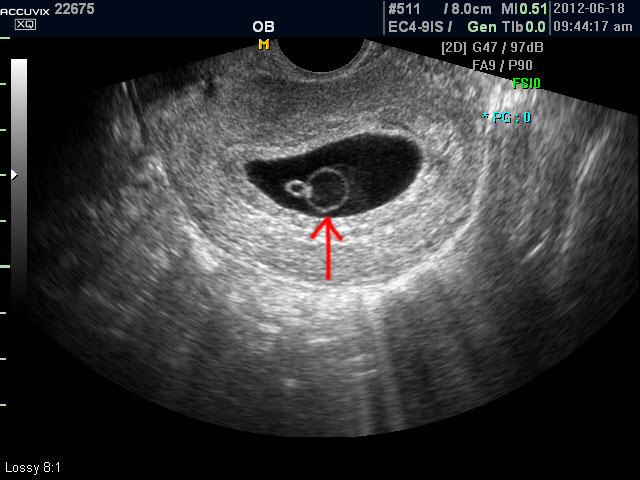

유산이란 임신 20주 이전에 어떤 원인에 의해서건 배아 또는 태아가 정상적으로 자라지 못하게 되어 자궁 내에서 사망하거나 체외로 배출되는 경우를 말합니다. 임신 4개월에서 5개월 무렵에 주로 유산되는 자궁 경관 무력증에 의한 유산을 제외하고는 이런 자연 유산의 80%는 임신 12 주 이내인 초기에 주로 발생합니다. 유산의 진단은 임신 증상의 소멸이나 질출혈로도 어느 정도 짐작이 가능한 경우가 있지만 최종적인 판단은 혈액 검사나 초음파 검사를 통하여 하게 되며 대개의 경우 초음파 검사로 확진을 하게 됩니다. 초음파 검사에서는 정상 임신으로 진단된 후 아기집 (태낭. G-Sac)이 보이지 않거나 평균 임신 주수에 비하여 아기집이 상당히 작을 때, 그리고 임신 8주 이후에 태아 심박동이 없는 경우에 유산일 가능성이 높다고 판단합니다. 아래는 유산과 관련된 초음파 사진으로 위 사진은 유산기가 있다고 하는 경우 (의학적으로는 절박유산)의 사진이고 아래의 사진은 고사 난자라고 하여 태아가 정상적으로 형성되지 못한 유산의 사례입니다.

1. 절박 유산 임신 20주 이내에 혈액이 섞인 질분비물이 있는 경우를 말하며 흔히 유산기가 있다고 말하는 경우입니다. 약 반수에서는 실제로 유산이 되며 유산이 되지 않고 임신이 지속되었을 경우 조기 분만이나 저체중아 분만, 주산기 사망의 위험이 높아지는 것으로 알려져 있지만 태아 기형의 빈도가 더 높지는 않습니다. 이런 절박 유산에서 치료는 침상 안정이 거의 유일한 치료이며 필요시 진통제를 쓰기도 하지만 흔히 유산 방지제로 쓰이는 황체 호르몬 공급은 의미가 없다고 합니다. 그리고 주기적인 초음파 관찰을 통하여 태낭과 태아의 발달을 확인해야 합니다.